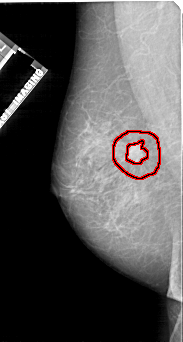

FILE: A_1112_1.LEFT_CC.OVERLAY

TOTAL_ABNORMALITIES 1

ABNORMALITY 1

LESION_TYPE MASS SHAPE IRREGULAR MARGINS SPICULATED

ASSESSMENT 5

SUBTLETY 5

PATHOLOGY MALIGNANT

TOTAL_OUTLINES 2

BOUNDARY

CORE